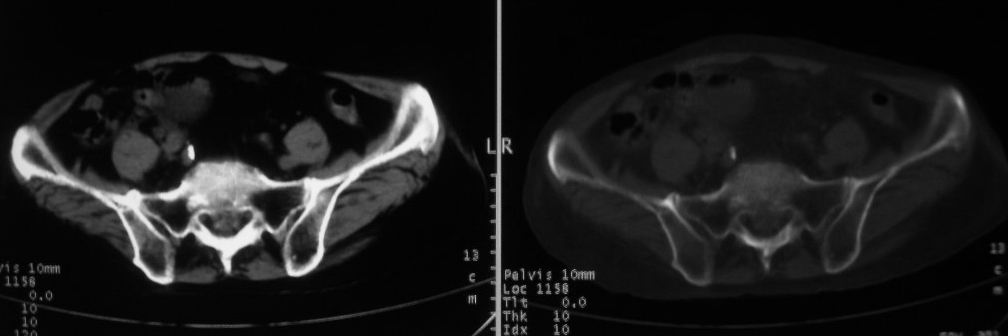

以下是引用zjzjr在2008-10-3 12:59:00的发言:[br]前列腺癌伴左髂骨\\腰椎转移可能性大.

以下是引用卜一在2008-10-3 13:40:00的发言:[br]前列腺癌!左髂骨\\腰椎转移?建议行全身骨扫描!

以下是引用深泽交通医院在2008-10-3 15:33:00的发言:[br]前列腺实性增大伴分叶状,与包膜间隙境界不清;椎体松质区间结节样密度影,考虑:前列腺癌,并椎体成骨性转移